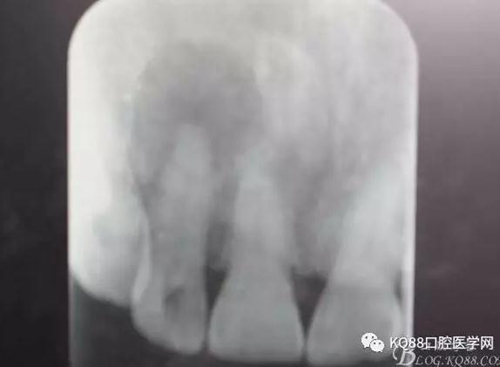

圖1.患者在根管術(shù)前的根尖片影像檢查:12有開髓孔,根尖有橢圓形陰影。